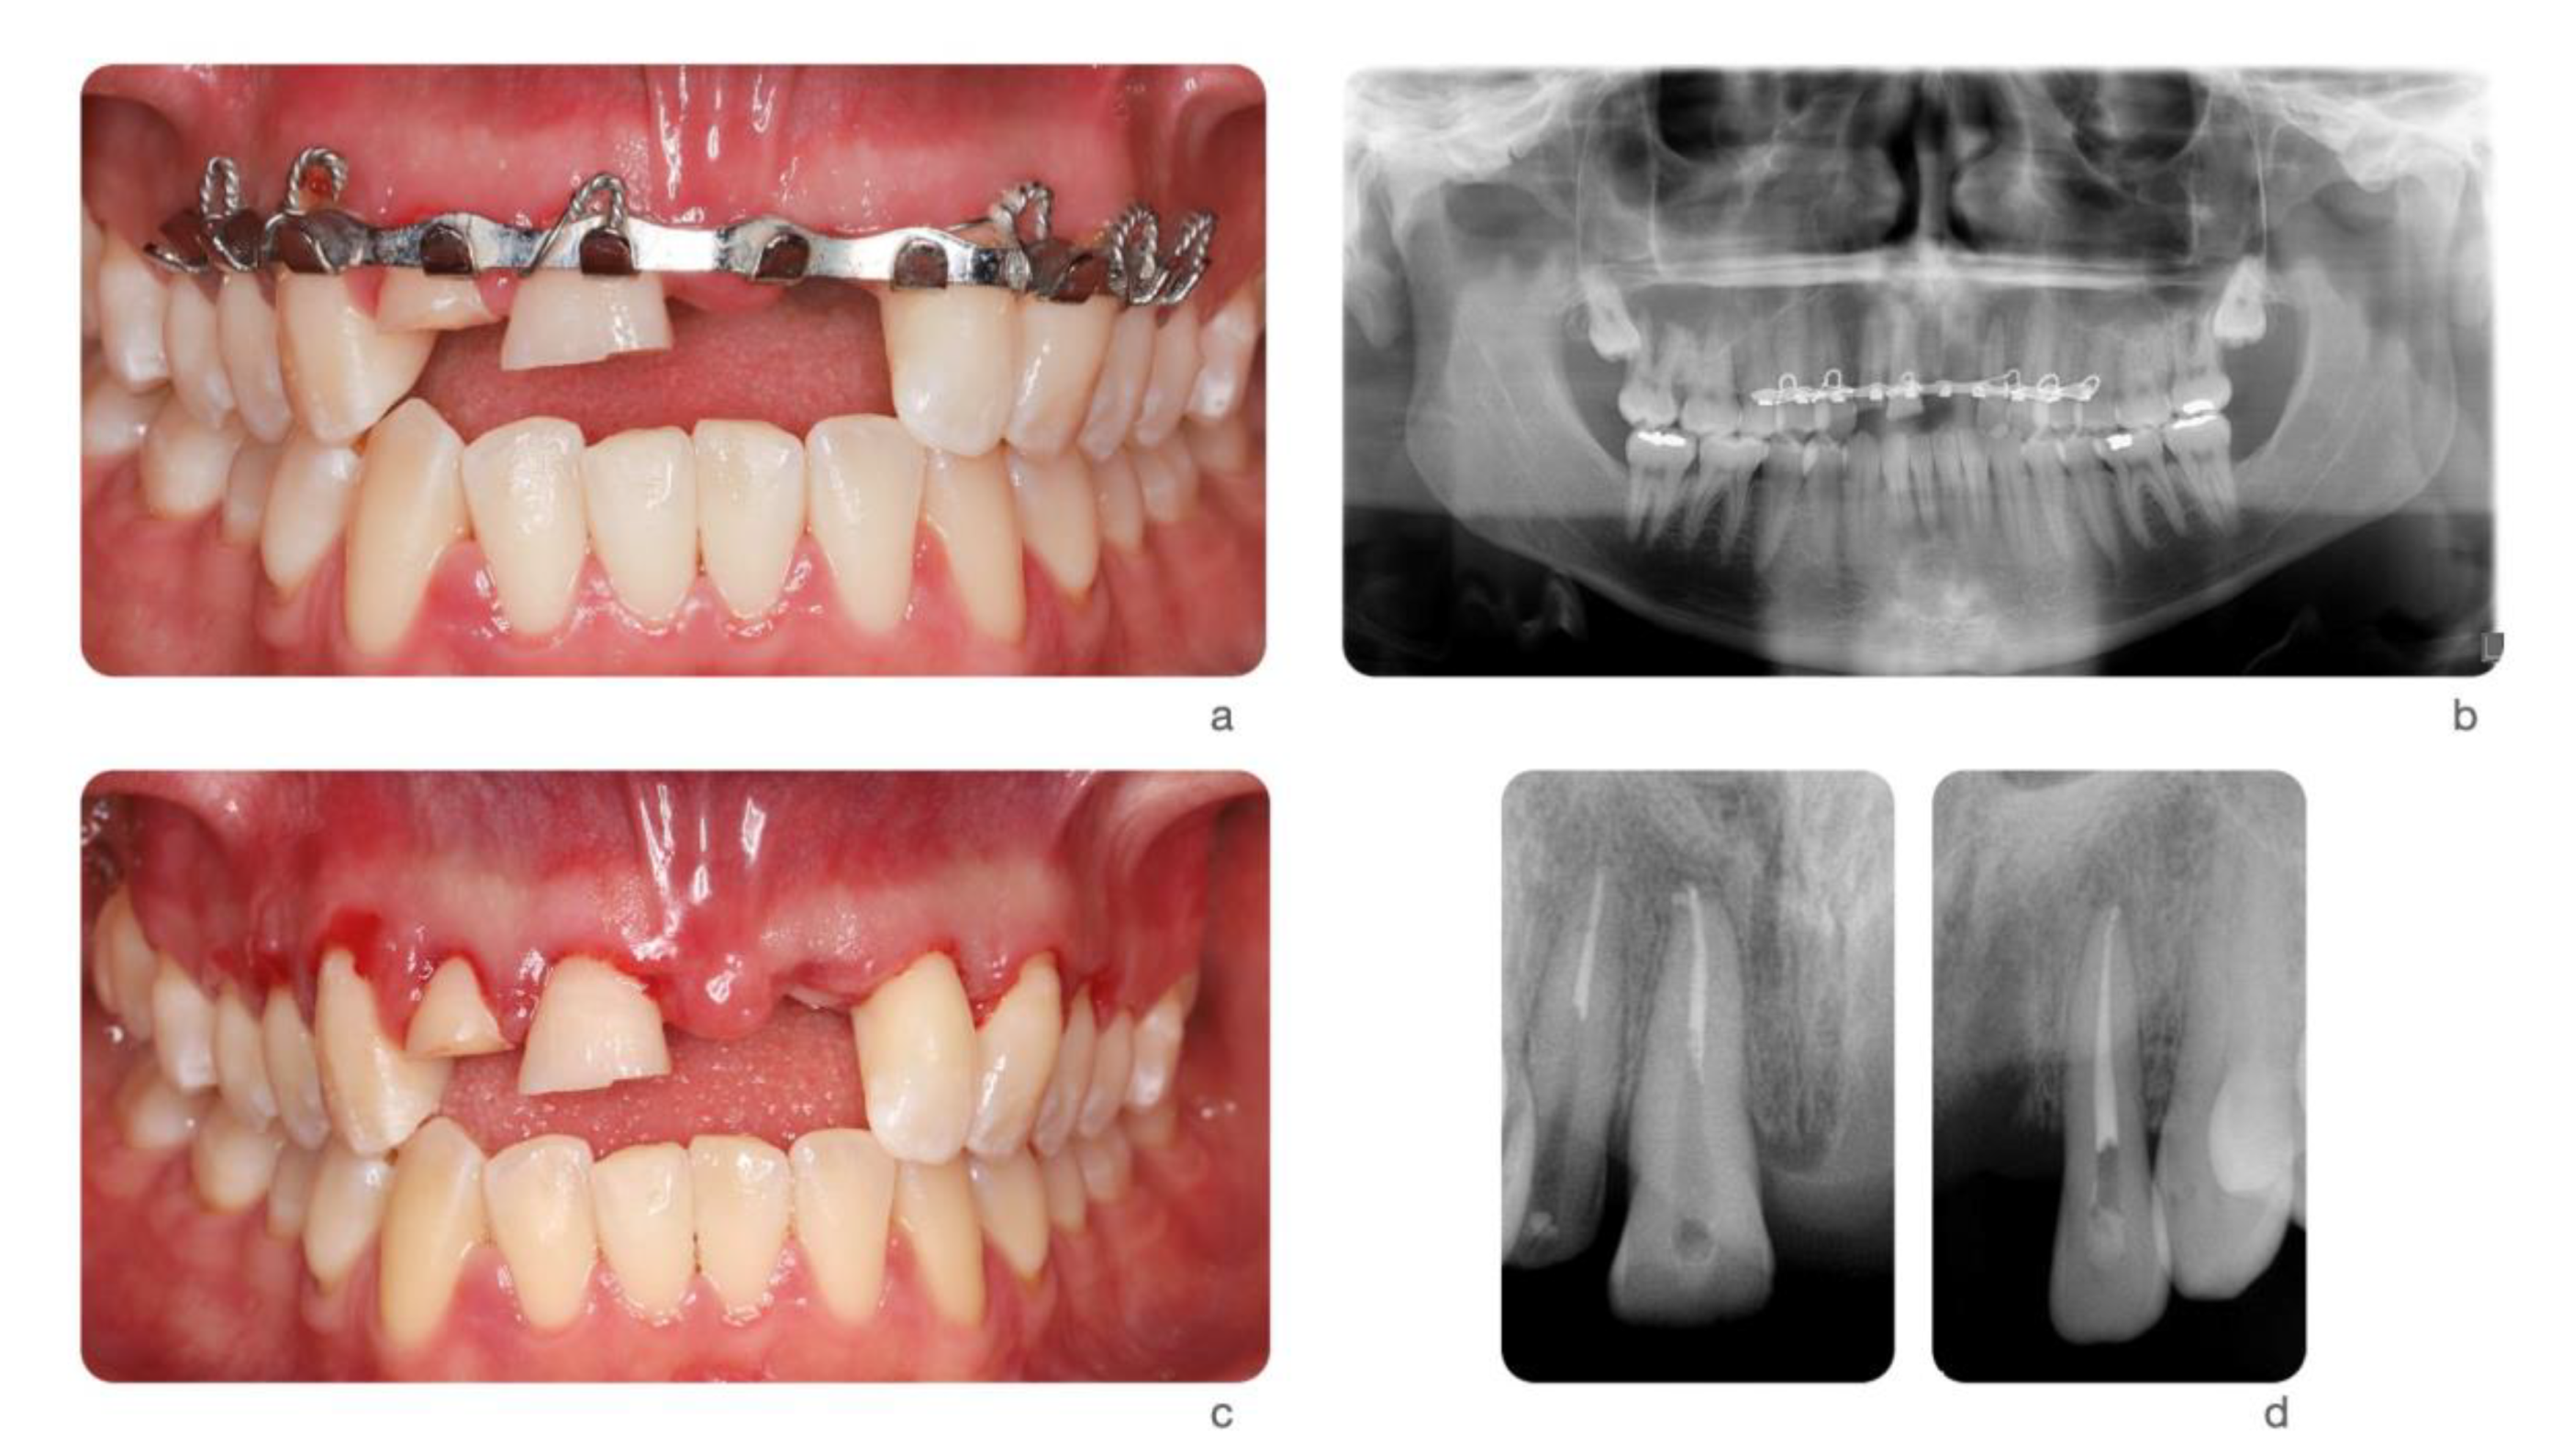

Figure 4.

A 24-year-old female fell from her bike during a race. She hit the tarmac and resulted in losing teeth#9, 10 and 11 (a,b) as well as a portion of the alveolar bone (c) as seen on the 3D print of the maxilla. An incisal chip on tooth #8 completed the damage of the fall. After an analysis of residual hard and soft tissue volumes, a digital wax-up was created to plan the future implant placement and restorations (d). Guided tissue regeneration was performed, and implants were placed in a Type 4 timeline (e,f). A provisional fixed partial denture and connective tissue graft were inserted to improve esthetics and tissue conditioning (g).